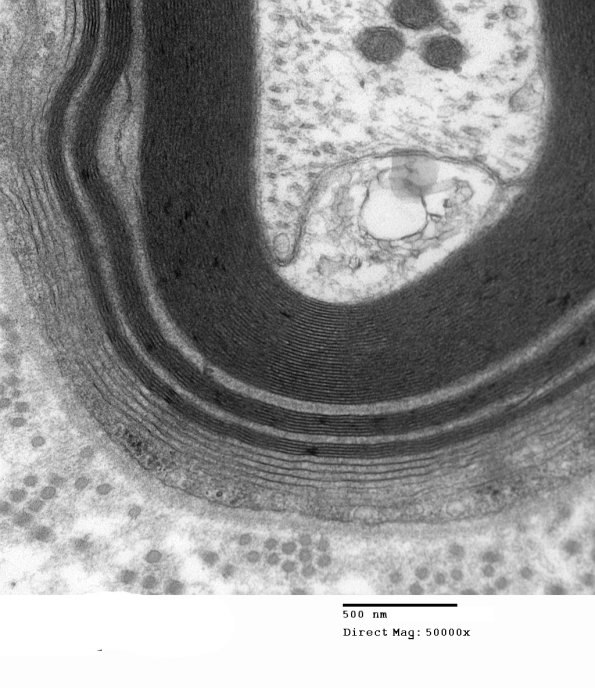

1E8B Anti-MAG NP (Case 1) EM 006 - Copy

Additional WSM involving this axon. (electron micrograph)